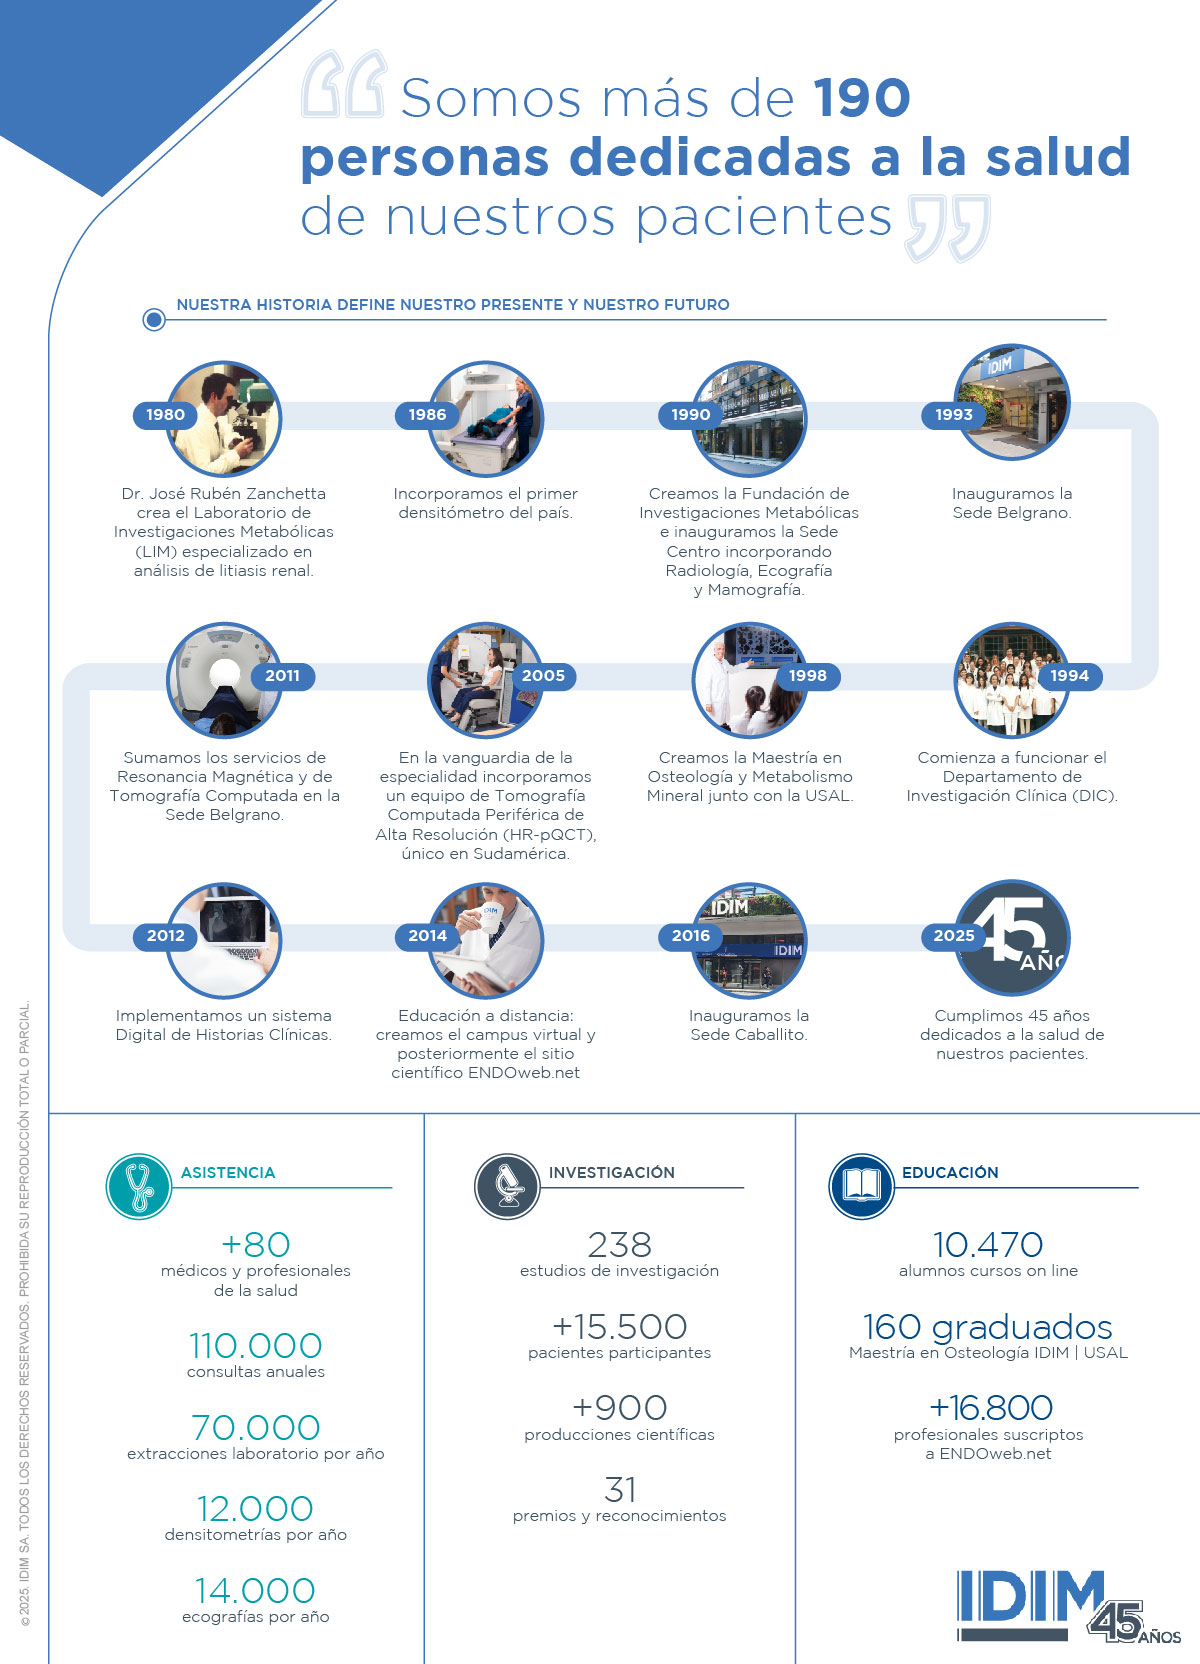

Desde hace 45 años estamos comprometidos con la salud y el bienestar de nuestros pacientes. Por eso brindamos servicios de calidad, enfocados en el área general de la endocrinología. Desde nuestros inicios, creemos que la excelencia se garantiza mediante la capacitación constante, la docencia y la investigación científica. Estamos convencidos de que nuestra labor debe orientarse a la situación del paciente. Somos nuestros pacientes.

Dr. José R. Zanchetta